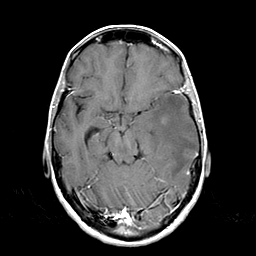

Metastatic bronchogenic carcinoma: T1-weighted MR -- Slice #8

[Home][Help][Clinical] Slice 8